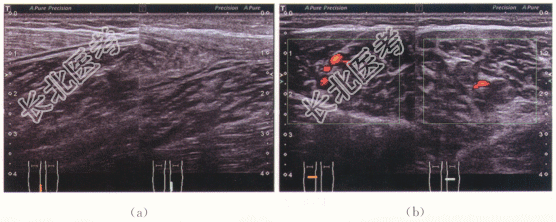

患者,男性,31岁,因“突发右小腿疼痛约2周”就诊。自诉打羽毛球杀球起跳发力后右侧小腿觉重物击打感,随后小腿疼痛,无缓解。既往无外伤史。

二、影像资料

- 简答题1、患者的诊断及超声依据是什么?